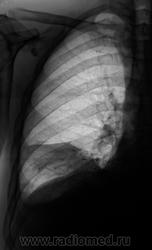

Пациент направлен на исследование с диагнозом "Правостороняя пневмония".

Междолевое осумкование выпота справа. Ну и конечно двустор.свободный.

Явная приподнятость диафрагмы настораживает...